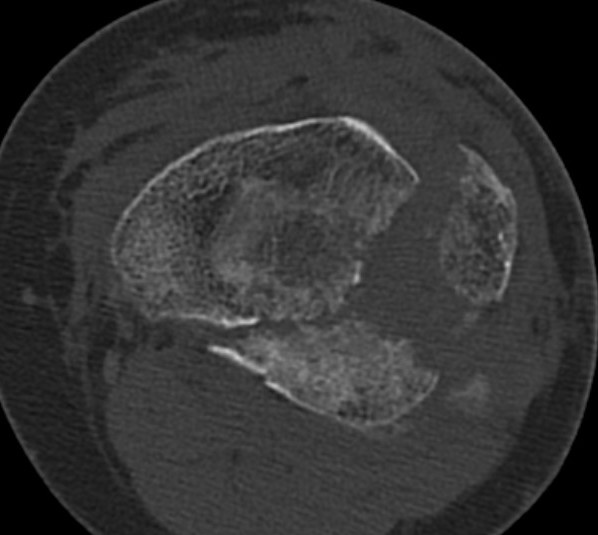

Schatzker Classification

I. Lateral Spilt

- seen in young patient

- lateral meniscus can be incarcerated in fracture

II. Lateral Split Depression

- often seen in young patients with high energy injuries

- vary in severity

III. Lateral Depression

- central depression usually seen in elderly

- have to create lateral cortical window in order to elevate fragment

IV. Medial plateau & intercondylar eminence

- high velocity injury associated with ACL / LCL / CPN injury

- can be low injury / osteoporotic and often unreconstructable

V. Bi-condylar + intact metaphysis

- unstable

- requires ORIF

VI. Bi-condylar + metaphyseal fracture

- fracture separating metaphysis from diaphysis

- highest incidence of vascular injury